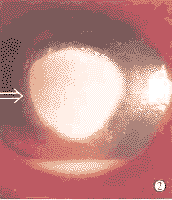

图2 棘阿米巴角膜炎 盘状溃疡合并前房积脓

Fig.2 Acanthamoeba keratitis Disciform ulcer with hypopyon

2.1 棘阿米巴感染角膜各阶段的临床表现分析 患眼皆急性发病,因眼红痛、畏光、流泪就医。开始视力无大影响,眼睑水肿、结膜充血、无分泌物。初表现上皮性角膜炎,光泽差,表面粗糙不平。裂隙灯下上皮层内见淡灰色细微点线状微隆起病灶,簇集或假树枝形排列,荧光素不着染或淡染,另见点状上皮剥脱。随上皮下出现斑、片状浸润,刺激症状明显,混合充血重。角膜旁中心区基质见向周边放射走行的纤细混浊。上皮层反复剥脱形成不规则形溃疡。角膜中周部基质弧、环形浸润、溃疡(图1),角膜缘肿胀、充血,视力锐减。角膜盘状浸润,中心浓密斑状混浊,进展为盘状溃疡(图2)。溃疡面粗颗粒状,浸润致密固着,边缘屡见沟状溶解。主病灶周围有时见卫星灶。虹膜充血、肿胀,前后粘连。重度前房反应,反复积脓、积血,多继发青光眼,并发晶状体混浊。病程中症状可短暂缓解随即进行性加重,常历时数月经年,最后全角膜混浊,溃疡、脓疡或后弹力层膨出、穿孔。患者诉重度眼痛(73.1%)而角膜知觉减退或消失(92.3%)。病初明确记载上皮性角膜炎11眼(42.3%)。上皮剥脱3眼(11.5%)。病程中先后表现浅基质浸润16眼(61.5%)。角膜神经周围炎4眼(15.4%)。地图状溃疡6眼(23.1%)。弧、环形浸润、溃疡15眼(57.7%)。盘状浸润、溃疡11眼(42.3%)。角膜缘炎4眼(15.4%)。虹膜睫状体炎23眼(88.5%),前房积脓11眼(42.3%),积血2眼(7.7%)。巩膜炎1眼(3.8%)。继发青光眼4眼(15.4%)。并发白内障2眼(7.7%)。膜细胞学检查未见包涵体、细菌或真菌。渗出细胞以中性粒细胞为主,屡见活化巨噬细胞。查见阿米巴包囊或/和滋养体16眼(16/18,88.9%)(图3)。普通细菌培养阴性19眼(19/22,86.4%)。真菌培养阴性22眼(22/22)。角膜刮取物分离培养出阿米巴11眼(11/19,57.9%)。3例戴接触镜患者的镜用生理盐水(3/4)及3例的镜盒(3/5)分离出阿米巴。虫株鞭毛试验未见梨形体,无鞭毛,滋养体及包囊的生物形态符合棘阿米属原虫。